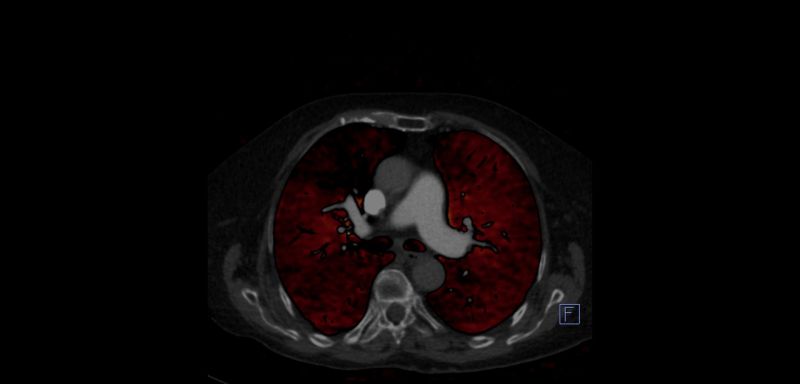

OLGU 2.

Normal tomografide PTE demostre edilememiştir. Dual BT Perfüzyon BT ile Kronik Pulmoner Emboli'si olan olguda sağ orta lobta perfüzyon defekti gözlenmektedir.